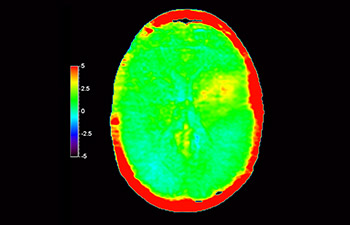

En una sociedad con una alta incidencia de trastornos neurológicos, Philips se compromete a ofrecer una excelente asistencia en el tratamiento y claridad en el diagnóstico para todos los pacientes. Hoy en día, aunque la RM es la modalidad de referencia para la adquisición de imágenes de neurooncología, su precisión a la hora de clasificar los tumores y de evaluar el seguimiento de los tratamientos aún tiene mucho margen de mejora. 3D APT (Amide Proton Transfer, transferencia de protones de amidas) es un exclusivo método de adquisición de imágenes por RM cerebral sin contraste que tiene por objetivo ofrecer un diagnóstico de neurooncología más fiable. 3D APT utiliza la presencia de proteínas celulares endógenas para producir una señal de RM que se corresponde directamente con la proliferación celular, que es un marcador de la actividad tumoral. 3D APT puede ayudar a los profesionales de la salud debidamente instruidos a diferenciar los gliomas de baja malignidad de los gliomas más graves, así como a diferenciar la progresión tumoral del efecto del tratamiento1.

con 3D APT